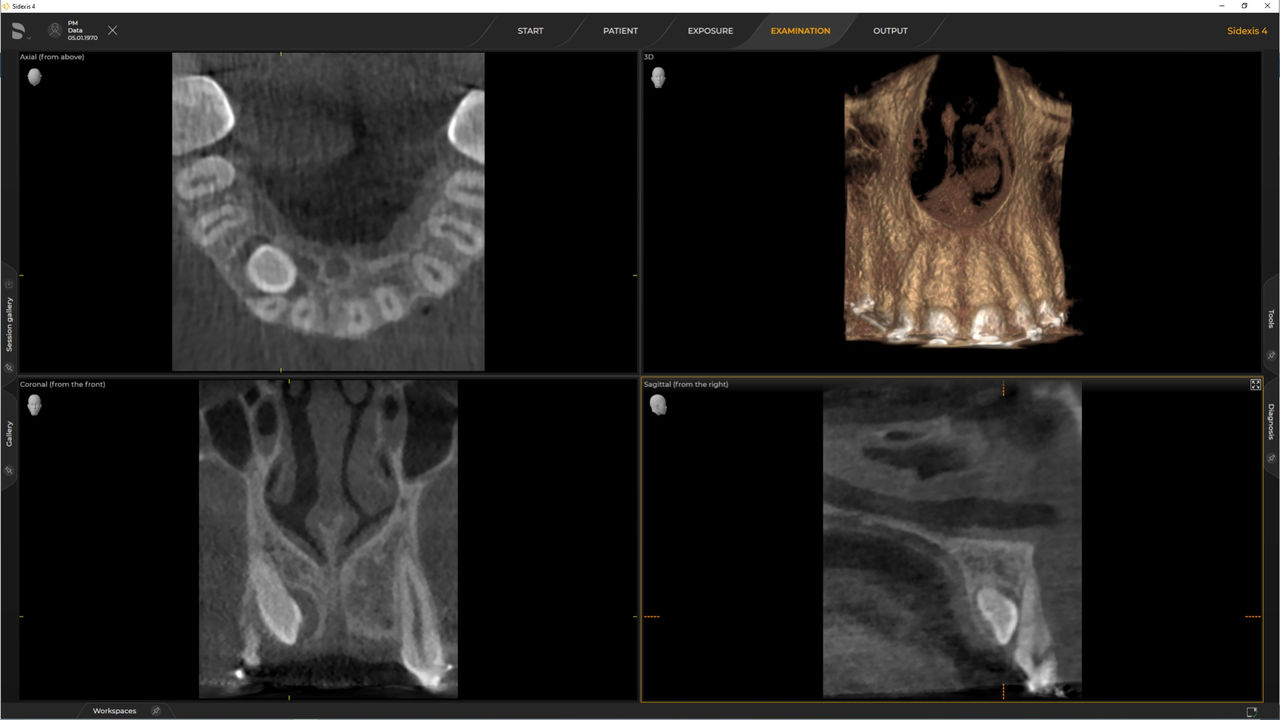

Das hochwertige 2D/3D-Röntgengerät mit umfassendem Leistungsspektrum für jede Praxis. Ob als reines 2D-Gerät oder mit integriertem 3D-Modul – Orthophos S ist ein zuverlässiger Partner und optimiert für alltägliche Aufgaben. Gestochen scharfe Aufnahmen dank CsI-Plus-Sensor und Autofokus. Die automatische Patientenpositionierung zusammen mit dem patentierten Okklusalaufbiss ermöglicht eine einfache und zeitsparende Patientenpositionierung. Für den Einsatz in der Kieferorthopädie ist der Orthophos S auch mit einem optionalen Ceph-Arm erhältlich. Und da Zukunftssicherheit für Dentsply Sirona wichtig ist, kann der Fernröntgenausleger jederzeit nachgerüstet werden.

Mit dem Intelligent Low Dose-Modus erhalten Sie 3D-Röntgenbilder im Dosisbereich einer 2D-Röntgenaufnahme. Im HD-Modus werden während eines einzelnen Umlaufs bis zu 1.400 Einzelbilder aufgenommen und zu einem 3D-Volumen mit bis zu 80 μm zusammengeführt. Der Vorteil für Sie: rauschärmere Aufnahmen in hoher Auflösung.

Ein breites Spektrum an Volumengrößen für verschiedene diagnostische und klinische Anforderungen von Ø 5 x 5,5 cm bis Ø 11 x 10 cm